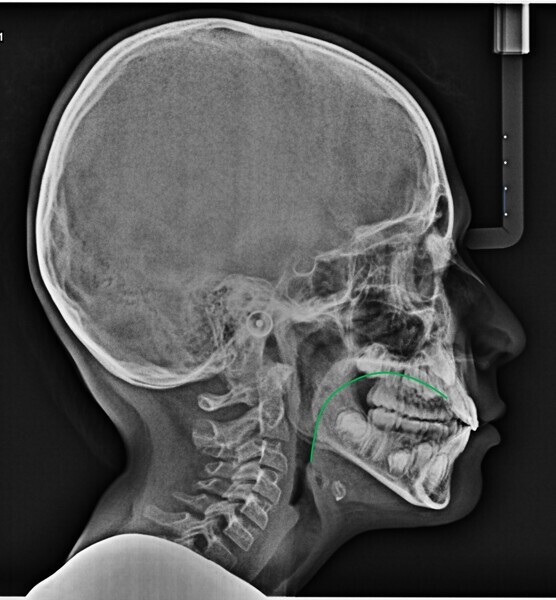

In my clinical practice, I prevent patients from rolling and rotating their heads using a cephalostat while allowing pitching: only after they have positioned themselves comfortably, do I place the post on the nasion, without exerting pressure. In this way, the patient will assume his or her habitual posture, and this too will be investigated by us. The cephalometric radiograph showed very important dysfunctional aspects (Fig. 4). Antero-rotation of the head and cervical hyper-lordosis were evident. Tracing of the tongue23 showed a very low position of the anterior part, as was found clinically. Cephalometric analysis was performed using the OrisCeph Rx1 CE program (Version 7.70; Elite Computer Italia). The patient showed a Class I skeletal pattern with antero-rotation of the maxillary plane, proclination of the mandibular incisors and increased anterior lower face height.

In the control cephalometric radiograph, the lingual position had completely regularised, the body and tip being in contact with the hard palate, creating an average overbite (Fig. 14). The cervical hyper-lordosis was moving towards correction and the skull posture was less forward.